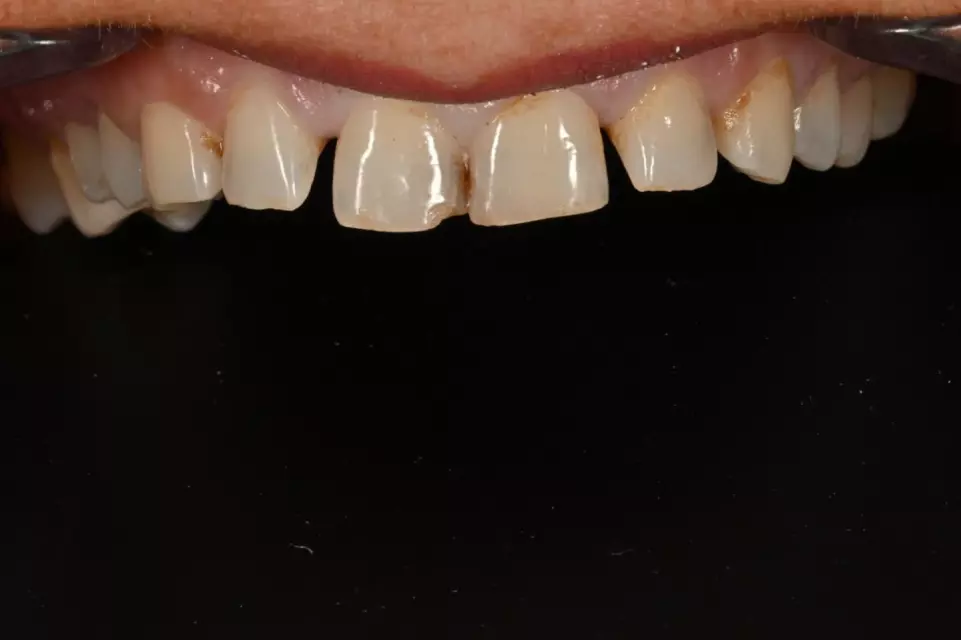

Ortodoncë: Drejtim i dhëmbëve dhe përmirësim i përtypjes me aparate fikse ose mobile bashkëkohore.